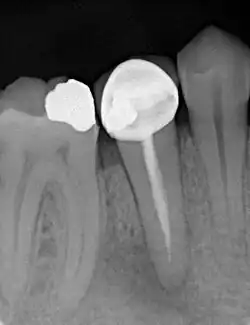

Anschließend wird eine ausreichend große Zugangskavität geschaffen und eventuell. vorhandene Wurzelstifte sowie das alte Wurzelfüllmaterial mit Spezialfeilen aus den Kanälen vollständig entfernt. Ganze Kanäle oder Kanalabschnitte, die bei der ersten Wurzelkanalbehandlung nicht behandelt wurden, werden zusammen mit den freigeräumten Kanälen auf ganze Länge bis zum natürlichen Ausgang an der Wurzelspitze aufbereitet. Ziel ist, die vollständige Durchgängigkeit der Kanäle zu erreichen. Im Kanalsystem verbliebene, abgebrochene Instrumentenfragmente aus der Erstbehandlung werden gegebenenfalls entfernt.[19]

Die vollständige Präparation der Kanäle erfolgt chemo-mechanisch, wobei für die Desinfektion des endodontischen Systems vorzugsweise mit Natriumhypochlorit, Ethylendiamintetraessigsäure (EDTA) und Chlorhexidin (CHX) gespült wird. In manchen Fällen ist nach der Aufbereitung die Applikation einer medizinischen Einlage in die Kanäle notwendig. Der Zahn wir dann provisorisch verschlossen und die Wurzelkanäle in einer weiteren Sitzung abgefüllt.

Das Wurzelkanalsystem wird, wie nach einer Erstbehandlung, definitiv mit einem volumenbeständigen und biokompatiblen Füllmaterial, meist mit Guttapercha, (1) verschlossen.